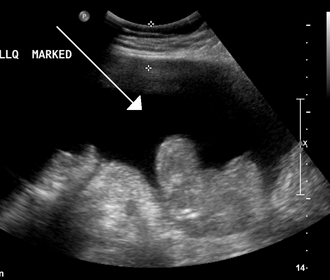

- Ultrazvuk: Manja količina se ovim pregledom može vidjeti ispod jetre ili u Douglasu. G